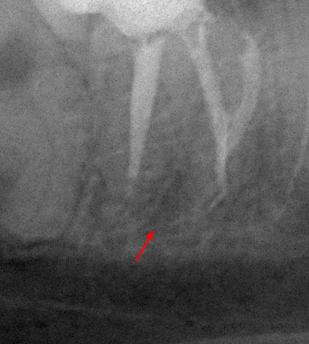

Пациентка 28 лет обратилась с жалобами на приступообразную ночную боль в области нижней челюсти справа.

На жевательной поверхности 47 зуба глубокая кариозная полость в пределах околопульпарного дентина, пульповая камера не вскрыта, зондирование болезненное, перкуссия безболезненная, холодовой тест резко болезненный, после удаления раздражителя болевая реакция продолжается в течении 20-ти секунд.

Диагноз: необратимый пульпит 47-го зуба.

На рентгенологических снимках представлена картина до лечения, диагностический снимок и конечный результат.